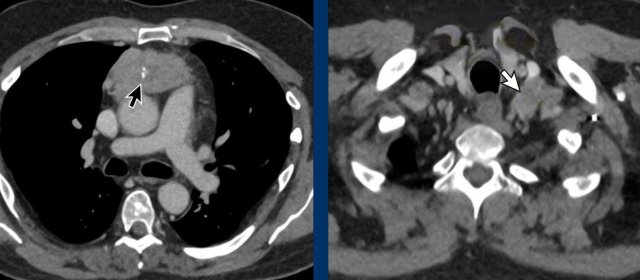

These images are of a 65-year-old woman with a history of Graves' disease, an autoimmune disorder that involves overactivity of the thyroid.

A CT was performed because of hemoptoe.

There is a large bulky thymus that contains macroscopic fat.

This is a typical picture of thymus hyperplasia.

Thymic hyperplasia in Graves' disease is related to excess thyroid hormones and thyrotropin receptor antibody.

It usually improves after successful treatment of Graves' disease.

Although not necessary, a MRI was performed.

Images

The out-of-phase fast gradient-echo image shows signal loss as we would expect.

The CT shows normalization of the thymus after treatment of the Graves’ disease.

When you measure the signal intensity, you will find a drop in signal intensity.

The percentage in signal drop is called the signal intensity index (SII).

Signal intensity index

The Signal intensity index (SII) is the amount of signal drop divided by the original amount of signal.

A SII more than 9% has a 100% sensitivity and specificity for the diagnosis hyperplasia.

The SII is more reliable than the chemical shift ratio.

In this case the SII was 77%.